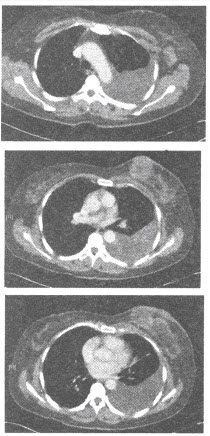

A:病因是食管神经肌肉运动功能障碍,下段食管括约肌呈失弛缓状态而导致食管张力减退、蠕动消失及食管扩张

B:临床上以吞咽困难、胸骨后疼痛及食物反流为最常见的症状

E:典型的X线表现为食管狭窄并其上段极度扩张